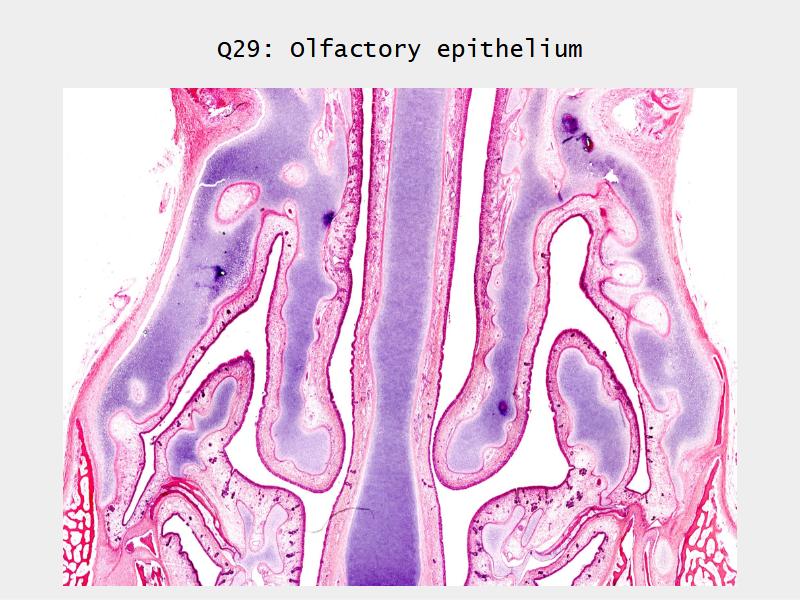

Slides: Respiratory System

- Slide 108: Olfactory epithelium

Olfactory epithelium

Function of the nasal cavity?

Function of the nasal cavity?

- Warm

- Moisture

- Filter

- Smell